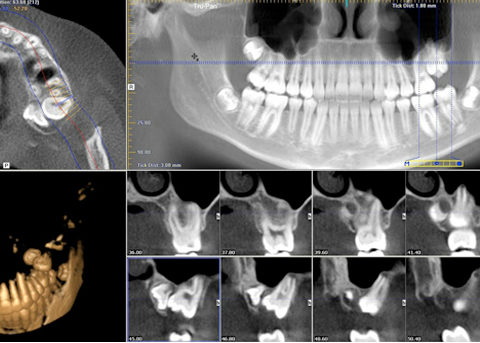

tac dentale - dentalscan

La TAC dentale aiuta il vostro dentista a individuare le anomalie emerse durante la panoramica dentale: è un esame di secondo livello approfondito, che può rendere noto lo stato di salute dell’osso su cui si intende installare protesi o nuovi impianti (TAC dentale roma). È consigliata per il suo basso grado di radiazioni (si ritiene…